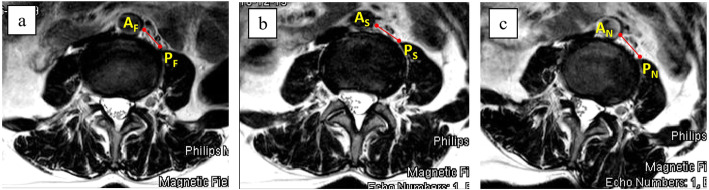

Three sequences of MRI (3 T, Ingenia, Phillips, USA, 2 mm cut) were done as follows: T1 and T2 sequences supine (with knees slightly flexed), T2 sequence in the right lateral decubitus with the left hip in a neutral position, and T2 sequence in the right lateral decubitus with the left hip in 45 degree-flexion. All images were then measured in the axial plane using the Picture Archiving and Communications System (PACS) by a spine surgeon and a radiologist. Measured at the mid-intervertebral disc height, we described the ROC at each level as the distance between A and B, where A was the left-most lateral border of the aorta (or the left iliac artery), and B was the most anteromedial aspect of the left psoas muscle (Fig. 1). Distances AB (ROC) were measured at each intervertebral disc level from L2/3 to L4/5 in all of the three sequences: the supine (ROCS), the right lateral decubitus with hip in neutral (ROCHN), and the right lateral decubitus with the hip flexed 45 degrees (ROCHF). The left psoas morphologies were manually delineated and calculated for the cross-sectional areas (PCA) after dividing the psoas muscle into 3 sections equally. The thickness of the anterior (APT) 1/3 of the psoas muscle was measured for comparisons (Fig. 2).

Fig. 1.

The retroperitoneal oblique corridor (ROC) measured in the three different positions; supine position: ROCS a, the right lateral decubitus with the left hip in flexion: ROCHF b, and the right lateral decubitus with the left hip neutral: ROCHN c. Noted the differences in left psoas morphologies and thickness